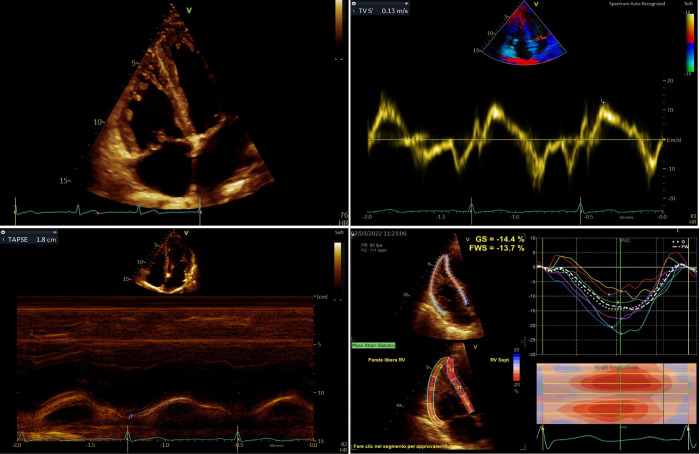

Background: Lung transplant (LUTX) candidates have subclinical right ventricular (RV) dysfunction, which has not yet been assessed by speckle-tracking echocardiography (STE)-derived RV free-wall longitudinal strain (RVFWLS). To evaluate the prevalence of RV dysfunction by RVFWLS and its relationship with conventional RV echocardiographic indexes in LUTX candidates.

Methods: In a single-center prospective observational cohort study, from January 2021 to March 2023 consecutive LUTX candidates underwent cardiac catheterization, radionuclide ventriculography, standard and STE. The diagnostic accuracy of RV ejection fraction by ventriculography (RVEF), tricuspid annular plane excursion (TAPSE), fractional area change (FAC), tricuspid peak annulus systolic velocity (S') versus RVFWS were computed.

Results: Thirty-four patients (female, 41%) with a mean age of 48 [36-59] years old enlisted for pulmonary fibrosis (35%) and cystic fibrosis (30%) were included. At cardiac catheterization, only 7 (23%) had pulmonary hypertension. Around 15-25% presented right heart enlargement. Tricuspid regurgitation was present in 20 (60%) of the patients. Median RVFWLS was -20.1% [-22.5%--17%], being impaired (> -20%) in 16 (47%) of the patients. RVFWLS identified the highest percentage (47%) of RV dysfunction, compared to TAPSE (32%), S' (27%), FAC (26%), and ventriculography (15%), which had very low sensitivity for detecting RV dysfunction compared to RVFWLS.

Conclusions: In patients enlisted for LUTX, RV dysfunction assessed by STE-derived RVFWLS is highly prevalent. STE can detect RV dysfunction better than standard two-dimensional echocardiography and ventriculography. Further studies are urgently needed to define the clinical implications and the prognostic value of RV dysfunction measured with RVFWLS.